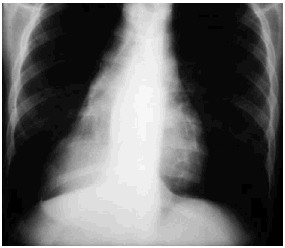

El esofagograma demostró una dilatación y atonía de los dos tercios superiores del esófago; el tercio inferior se encontraba desviado hacia la derecha por una compresión extrínseca redondeada (fig. 2).

Fig. 2.